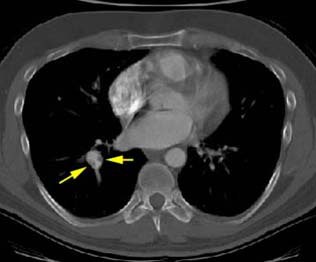

Helical CT permits reconstruction images along the course of the vessel. In this case the eccentric thrombus in the right lower lobe pulmonary artery is well seen: